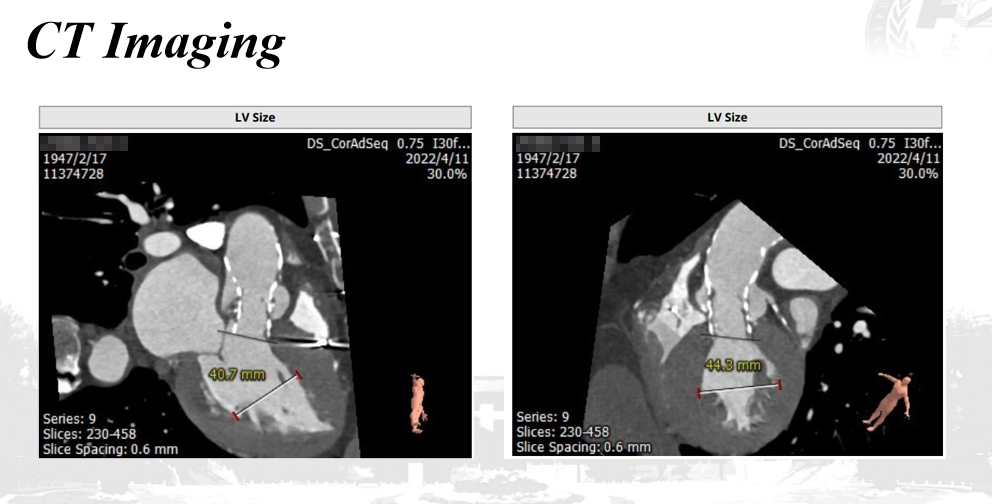

CT评估(TAVR术后):

1.CT评估(多平面测量)

TAVR瓣架低端为基准,测量瓣架上的2,4,6,8mm层面,直径都在22-23mm左右,原TAVR瓣架呈直筒状。

2.心室大小评估

心室大小尚可。